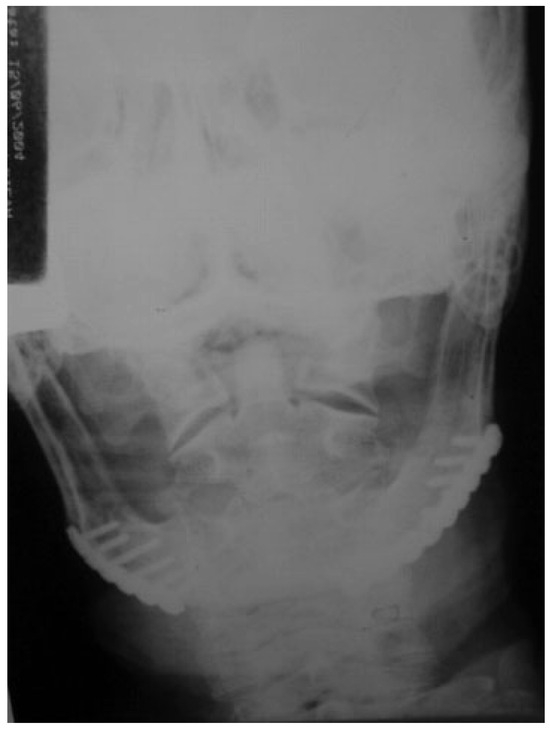

A 72-year-old man was referred to the University Hospital in June 2004 as a fall victim. After extraoral exam, mandibular X-rays showed two fractures at the left mandibular body, one in the left subcondylar region with minimal displacement and one at the right mandibular body (Figure 1 and Figure 2). The patient presented mouthopening limitation, and besides the painful symptomatology during palpation, the patient reported dysphagia and paresthesia of the mental nerve bilaterally and stated that he did not wear dental prosthesis.

Figure 1. Preoperative posteroanterior mandibular radiograph.